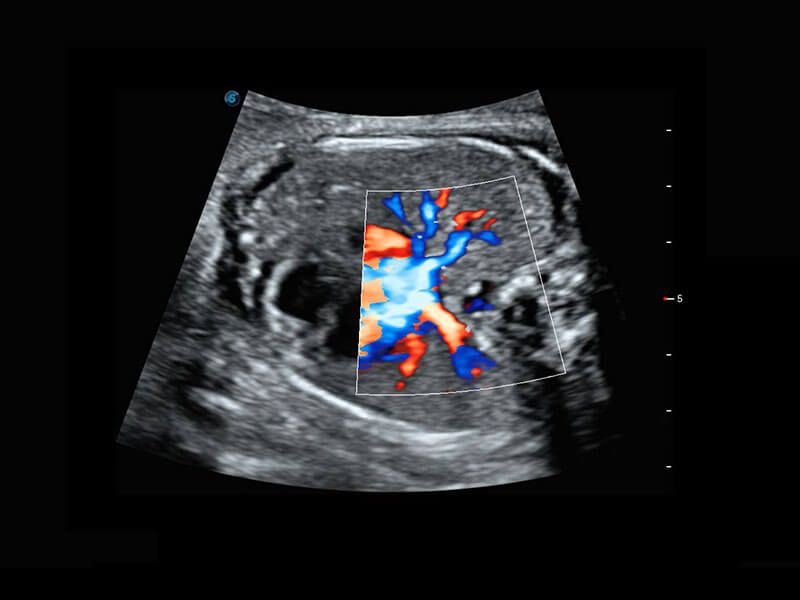

P60搭载宽频带线阵探头、宽景成像、弹性成像技术,为您提供乳腺应用方案。P60支持高频相控阵探头、线阵探头、腹部高频探头、腹部微凸探头等,丰富的探头群搭载敏感的彩色血流成像,适用于新生儿多种脏器检测要求,满足新生儿筛查需求。

乳腺导管癌

乳腺癌显微血流

新生儿肝血管癌

新生儿脊髓圆锥

新生儿心脏